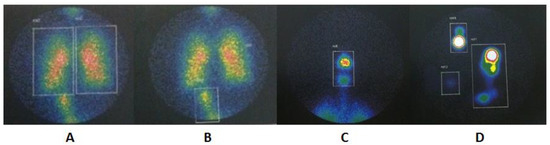

An illustration of pulmonary, extrapulmonary, and device ROI is shown in Figure 3. The results of the proportion of total aerosol represented in each ROI are presented in Table 2 and represented in Figure 4. A graphical analysis of the difference between the three device configurations in aerosol deposition to the lungs, upper airways, stomach, device total, nebulizer alone, and expiratory filter is shown in Figure 5.

Figure 3.

Pulmonary and extrapulmonary ROIs that are used to quantify aerosol deposition and calculated the mass balance across compartments including (A) total lung regions, (B) stomach, (C) upper airways, (D) nebulizer, adapter and expiratory filter.

The pulmonary deposition was greater with an MN with a VHC than the JN with and without a VHC (p < 0.001). The extrapulmonary aerosol deposition was higher with a JN without a VHC when compared to the other two modalities (p < 0.001), while we found no statistical or clinically relevant difference between the MN + VHC and the JN + VHC (Figure 5). Stomach deposition was greater with an MN + VHC compared to the JN with (p < 0.001) and without a VHC (p = 0.001) (Figure 4 and Figure 5).